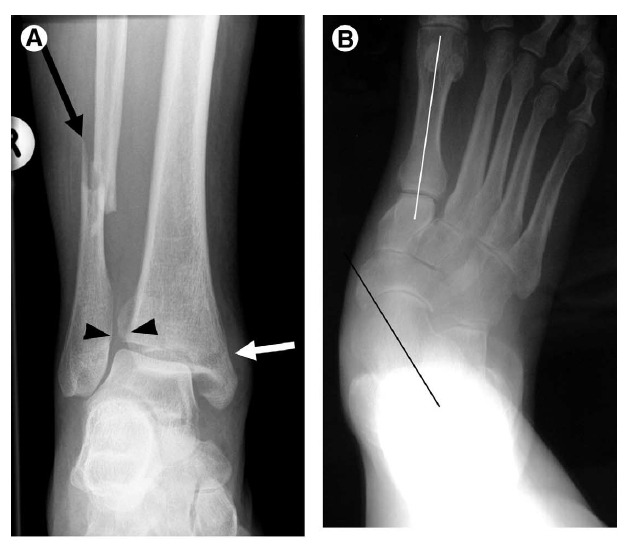

Figure 2 Malalignment.

(A) Syndesmosis disruption. Frontal view of the ankle shows a transverse medial malleolar fracture (short arrow) and fibular shaft fracture (long arrow) compatible with an eversion mechanism. Note widening of the distal tibiofibular syndesmosis (arrowheads) consistent with ligamentous disruption.

(B) Overpronation in posterior tibialis tendon dysfunction. AP view of the foot shows the orientation of the talus (black line) directed medial to the forefoot; normally this line intersects the first metatarsal shaft (white line). This indicates overpronation and is seen in the setting of posterior tibialis tendon dysfunction, often associated with pes planus and arch collapse.

(C) Lisfranc injury. AP view of the midfoot shows widening of the interval between the first and second metatarsal bases with offset of the medial edge of the second metatarsal (short arrow) compared with the medial margin of the second cuneiform (arrowheads) consistent with Lisfranc ligament injury. Note small avulsion (long arrow).

(D) Hallux valgus and bunion. AP view of the foot shows hallux valgus with bone proliferation at the median eminence (bunion deformity, long arrow) with lateral subluxation of the sesamoid bones (arrowheads). Note also mild bone proliferation at the lateral aspect of the fifth metatarsal head (short arrow) representing a bunionette. There is also abnormal widening of the angle between the first and second metatarsal shafts (metatarsus primus adductus).